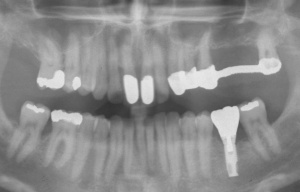

Der Erstbefund zeigte eine generalisiert entzündliche marginale Gingiva mit generalisierter Blutungsneigung bei Sondierung. Die approximalen Sondiertiefen waren durchgehend erhöht und betrugen im Molarenbereich bis zu 12 mm (s. Abb. 4). Es lagen multiple Zahnlockerungen vor, eine Zahnlockerung des Grades II zeigte sich an den Zähnen 11, 25, 26, 38, 37, 47; Grad III am Zahn 24. Harte Beläge in der Unterkieferfront, generalisiert weiche Beläge (API 62 %). Wurzelkaries an 24. Suffiziente Brückenversorgung im I. Quadranten. Die Panoramaschichtaufnahme von Juni 1998 (s. Abb. 4) zeigt einen generalisierten horizontalen Knochenabbau mit vertikalen Einbrüchen in regio 17, 25, 37 und 47. Interradikuläre Aufhellungen im Sinne einer Furkationsbeteiligung an 17, 26, 38, 37 und 47. Via falsa an 24.

a) Initialbehandlung vom 18.06.1998 – 27.10. 1998:

Gemäß den Vorgaben einer systematischen Parodontalbehandlung wurden zunächst mehrfache professionelle Zahnreinigungen mit Anleitung des Patienten zu einer effizienten häuslichen Mundhygiene durchgeführt. Hierbei konnte der SBI auf 15 %, der API auf 8 % gesenkt werden. Nach Abschluss der Initialtherapie im Oktober 1998 wurde ein entsprechender Parodontalstatus (s. Abb. 5) erstellt und mit dem Patienten der weitere Behandlungsablauf besprochen. Aufgrund der fortgeschrittenen parodontalen Destruktion musste eine Vielzahl von Zähnen als prognostisch fragwürdig beurteilt werden. Die Prämisse der Behandlung war jedoch, den Patient sowohl kurz- als auch langfristig möglichst mit einem festsitzenden Zahnersatz zu versorgen. Als nicht erhaltungswürdig wurden die Zähnen 24, 25, 37, 38 und 47 beurteilt.